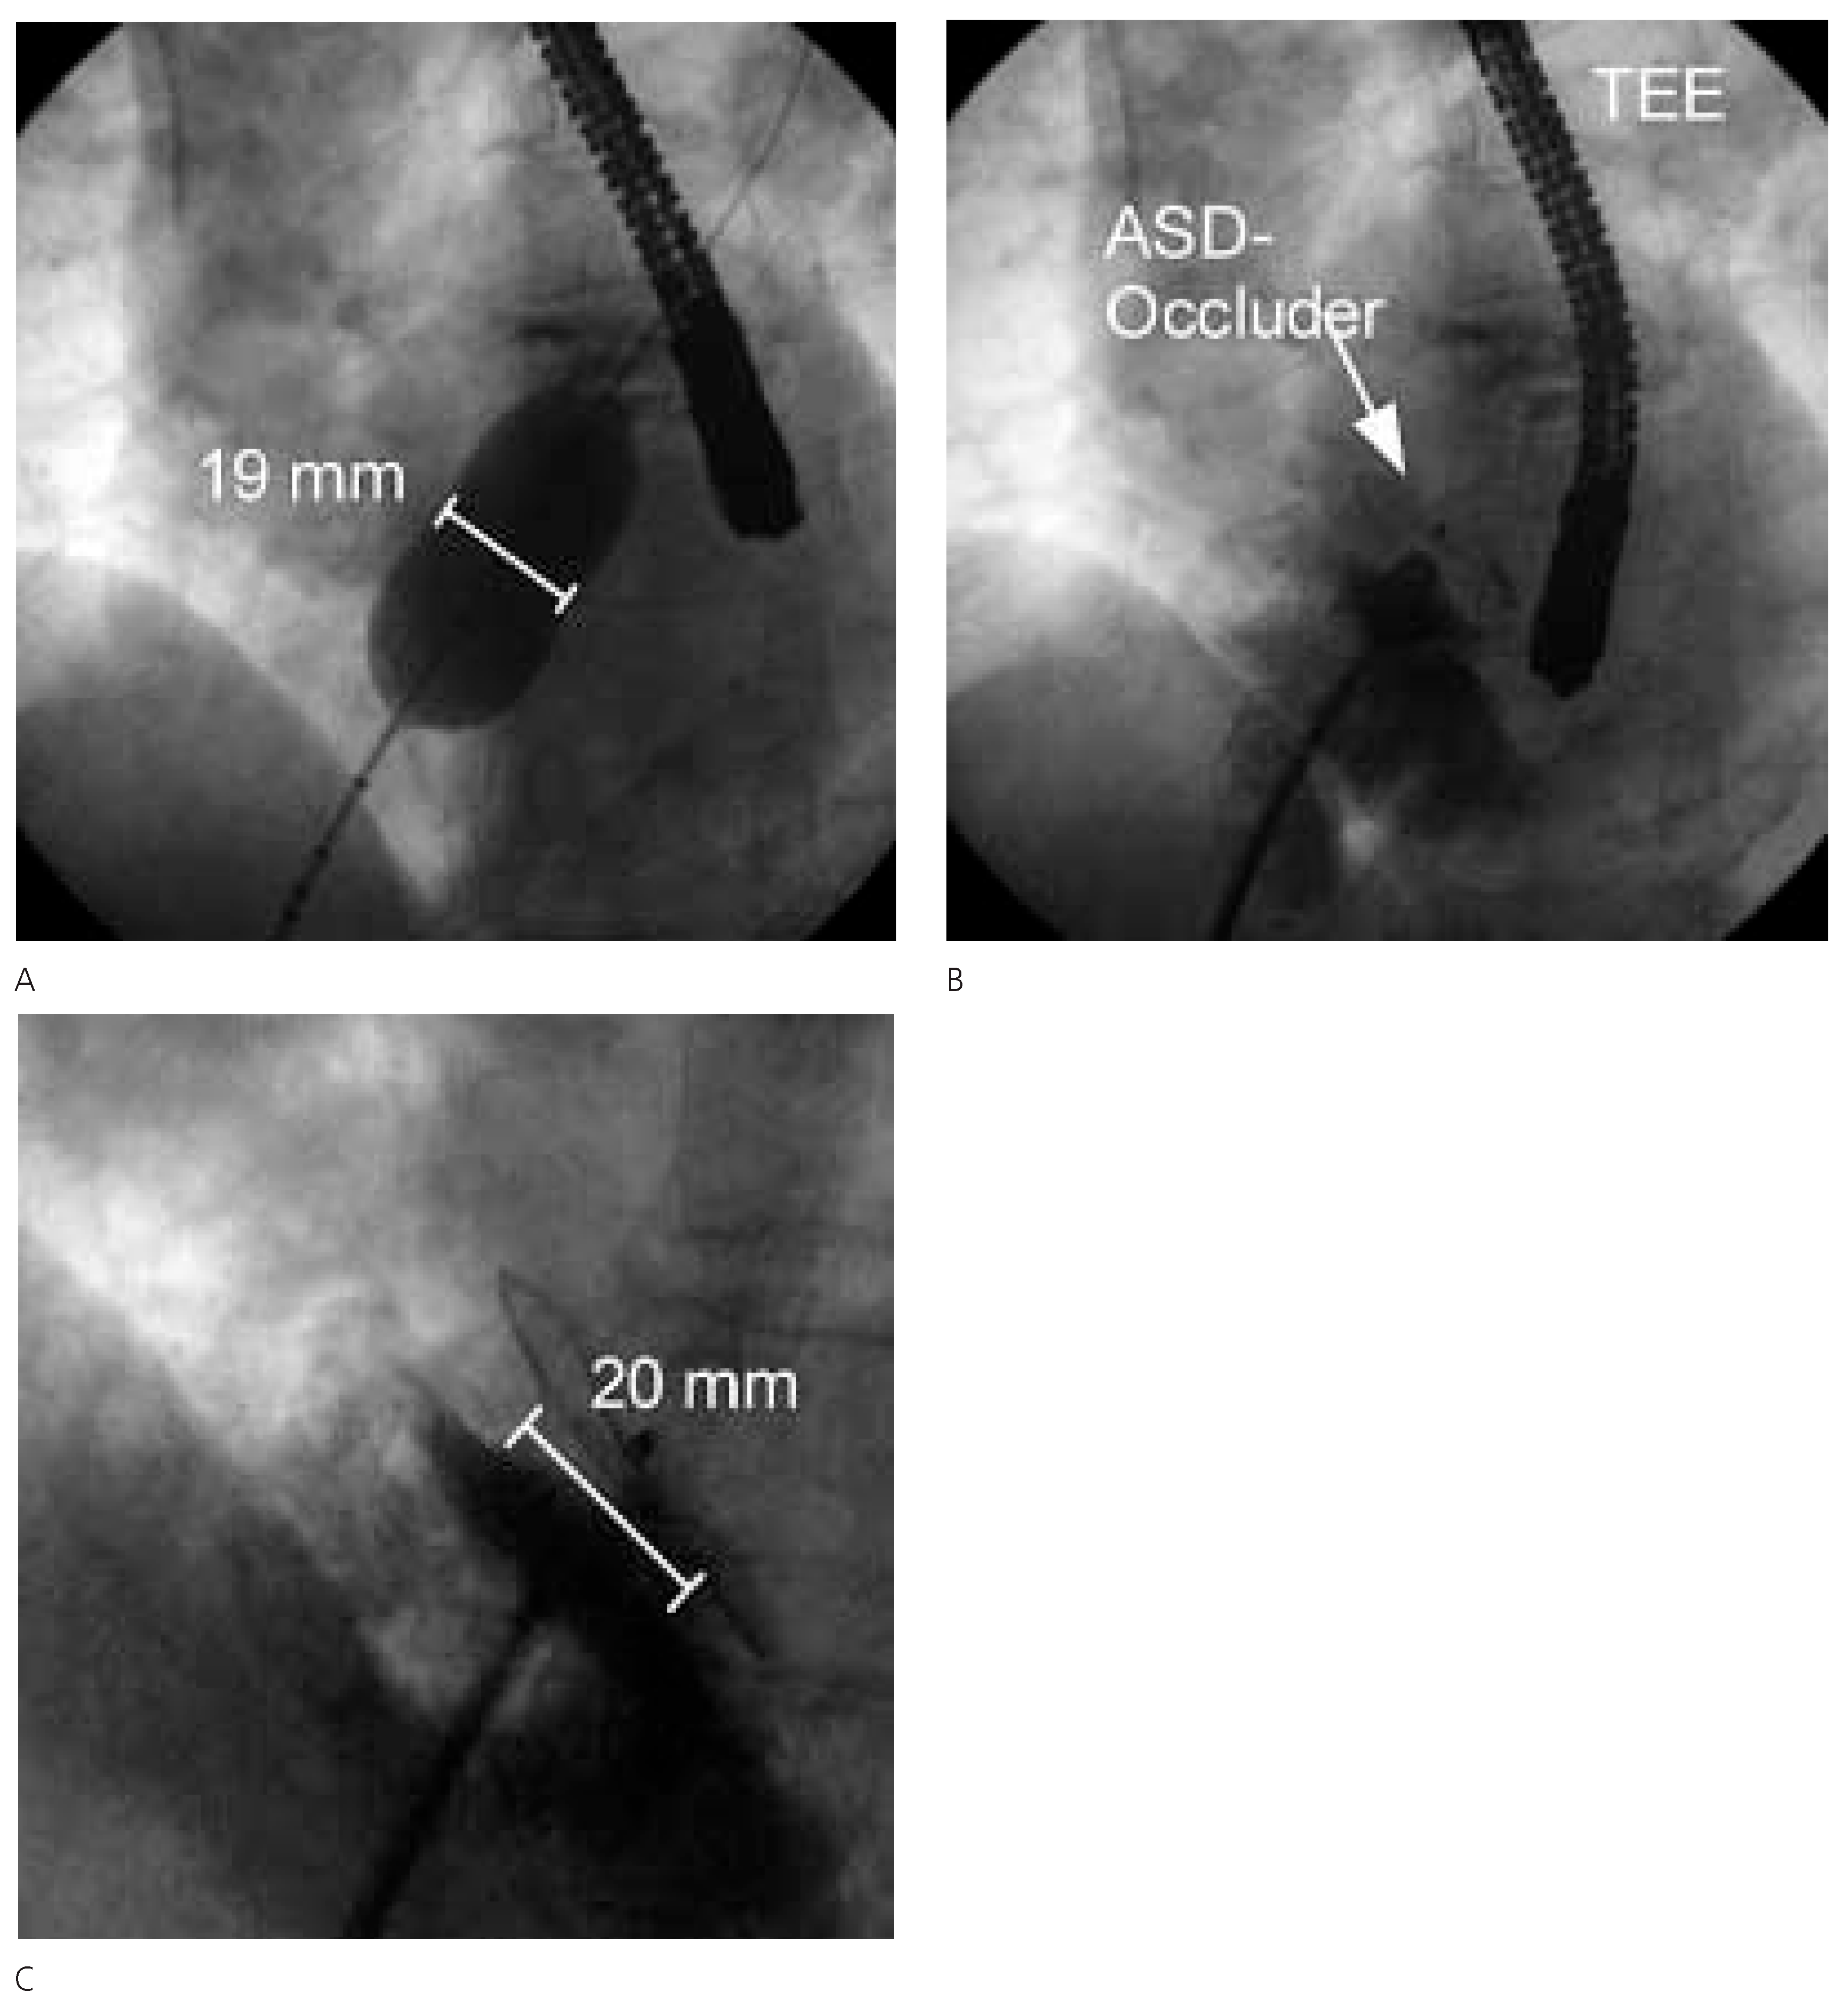

Figure 3.

TEE vor (A) und nach (B) Verschluss mit Amplatzer-Occluder 20 mm. Zu beachten die Position des ASD nahe der Aortenwurzel.

Figure 4.

A Ausmessen der ASDGrösse mittels Ballon. B Kontrolle der AmplatzerOccluder-Lage mittels TEE. C Amplatzer-Occluder in Position.